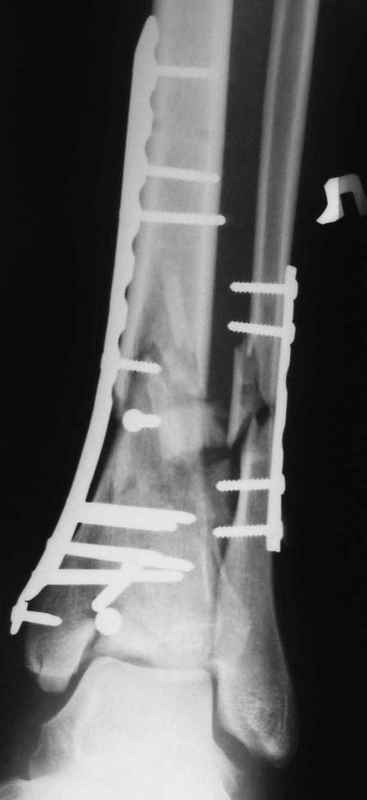

Др. Дрягин в своих случаях показал и правильно подсказывает методику АО, в первую очередь восстановление длины малоберцовой, а потом восстановление суставной поверхности и в зависимости от случая в дистальном эпиметафизе с костной пластикой.

Конечно, в идеале, если это возможно, применение современных фиксаторов без открытия места перелома с перкутанными и малоинвазивными пластинами с угловой стабильностью.

В настоящее время больной в реанимации по поводу Черепно Мозговой Травмы и состояние улучшается. Запланировал ушивание раны в пятницу, если позволит состояние мягких тканей и при отсутстви отека возможно удастся просунуть перкутанномедиальную пластину.

Классическая последовательность открытой редукции состоит из следующих этапов: 1-Восстановление длины и фиксация перелома малоберцовой кости

2 - Реконструкция суставной поверхности большеберцовой кости. 3 - Заполнение

метаэпифизарного дефекта свободным костным трансплантатом. 4 - поддерживающая фиксация с помощью накостных пластин.